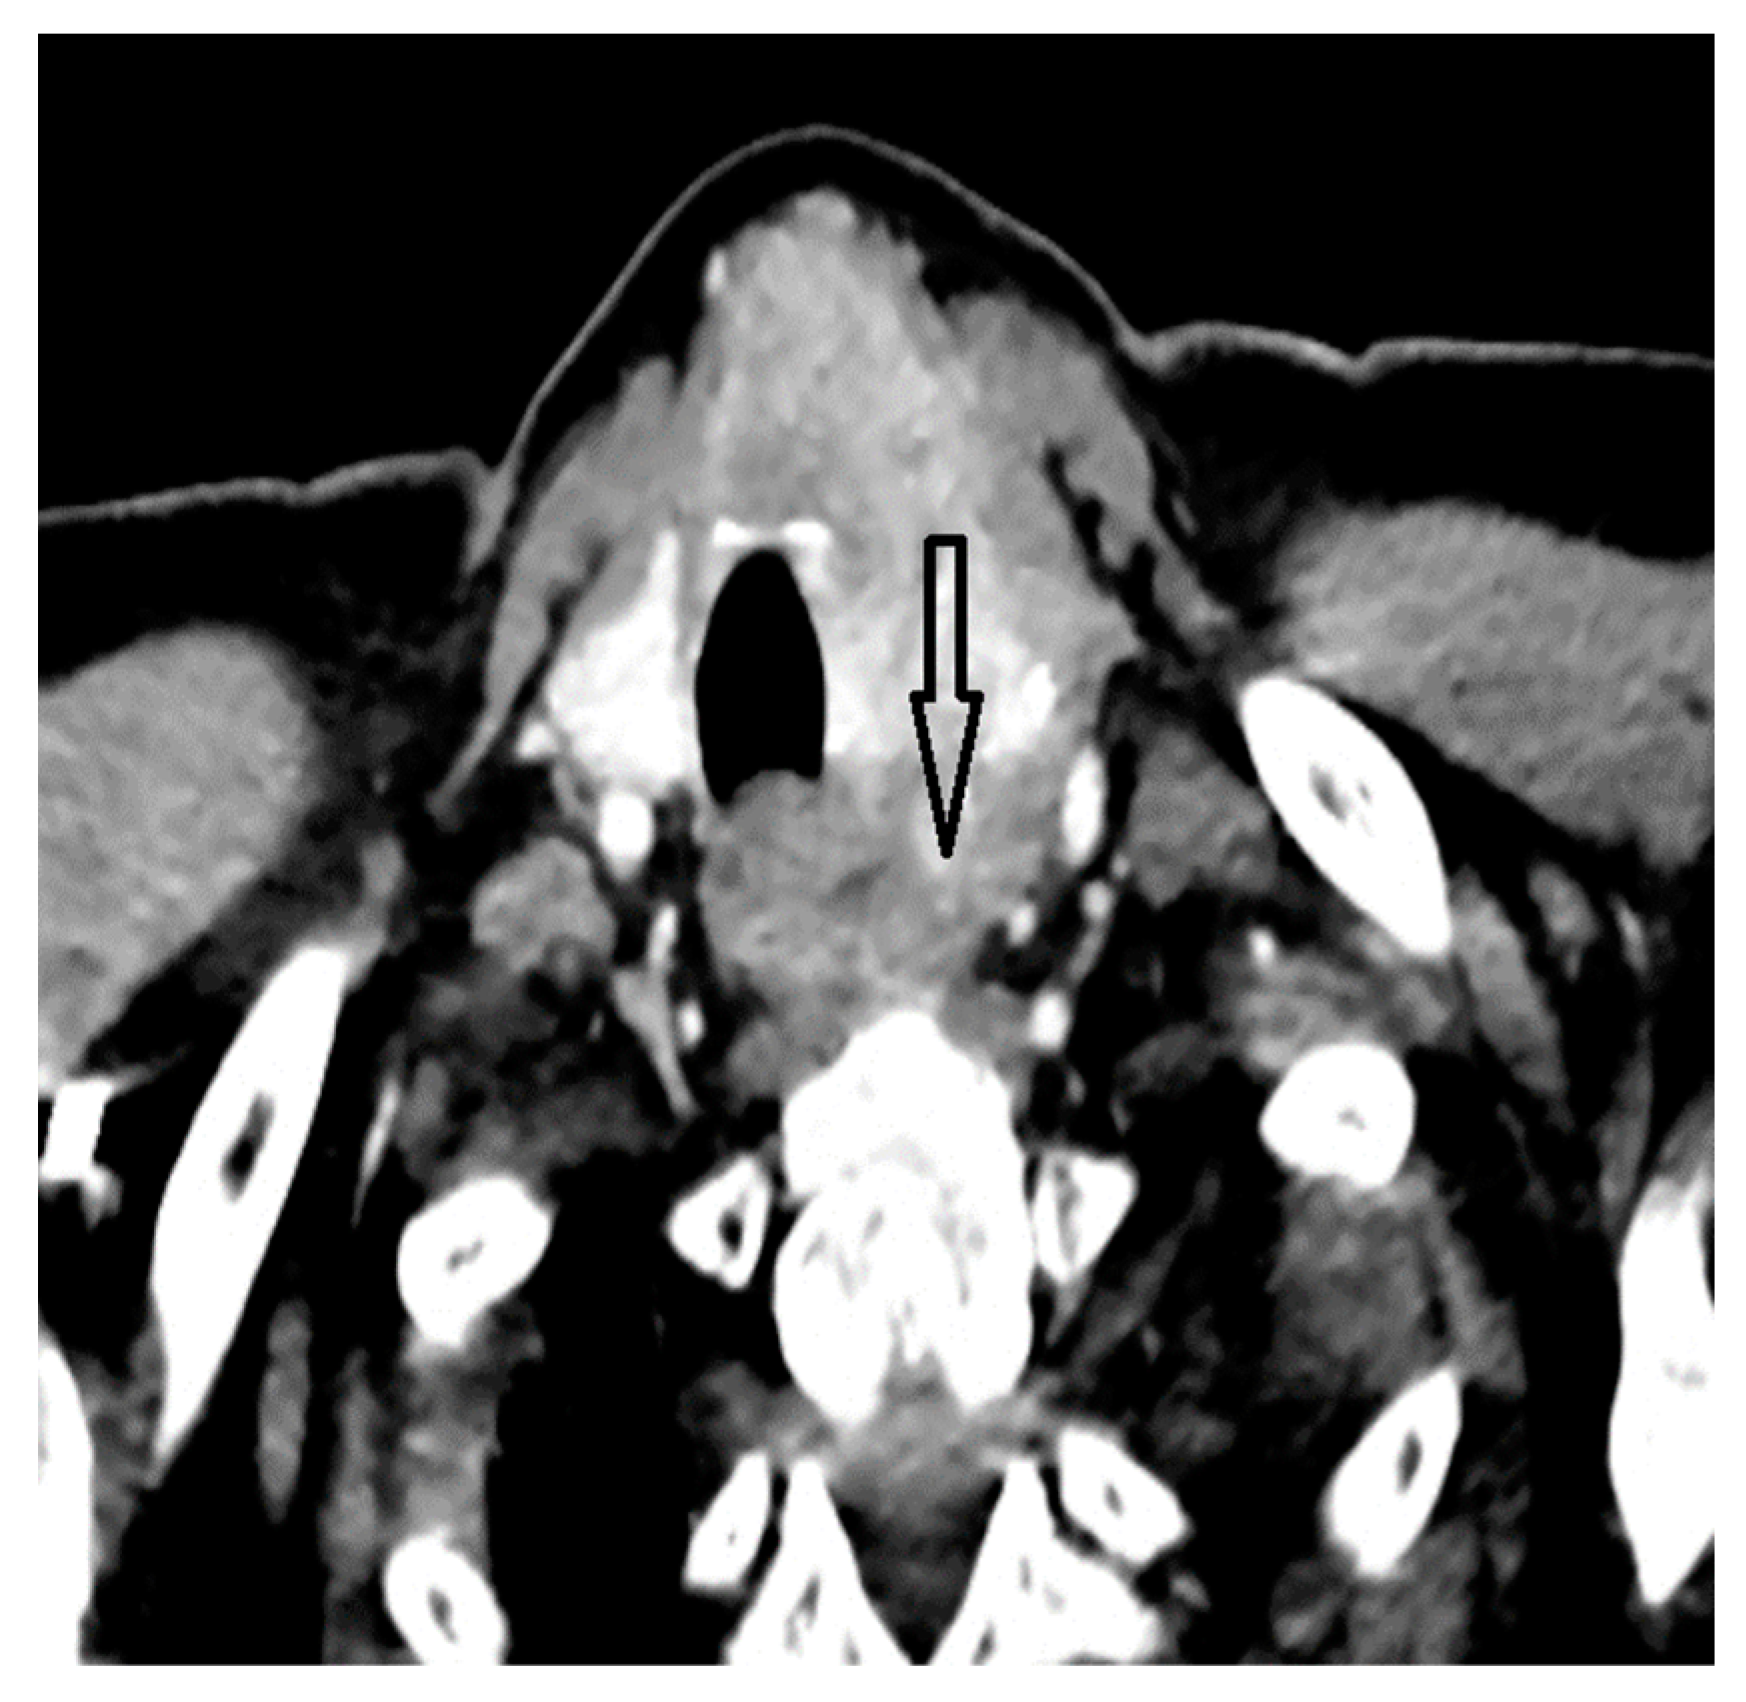

2. Case Report